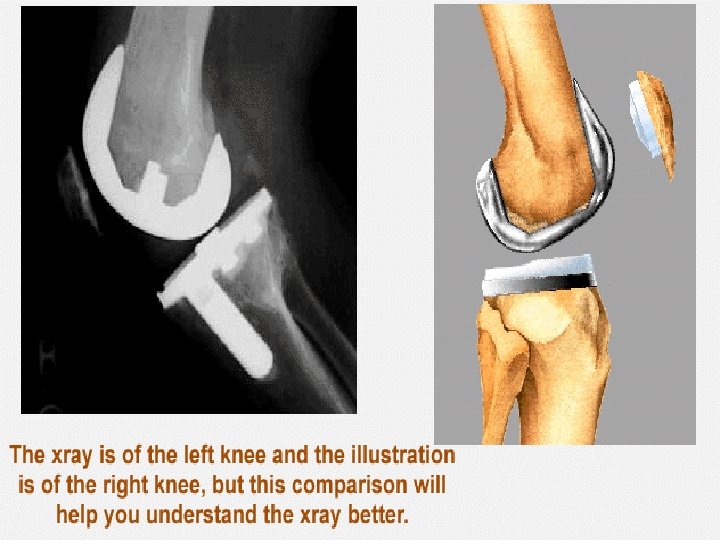

componenten

Hoe werkt het De computer detecteert gedurende heel de ingreep het been van de patiënt , het prothese materiaal en de instrumenten. n Virtuele fluoroscopie n De chirurg opereert n De computer navigeert n